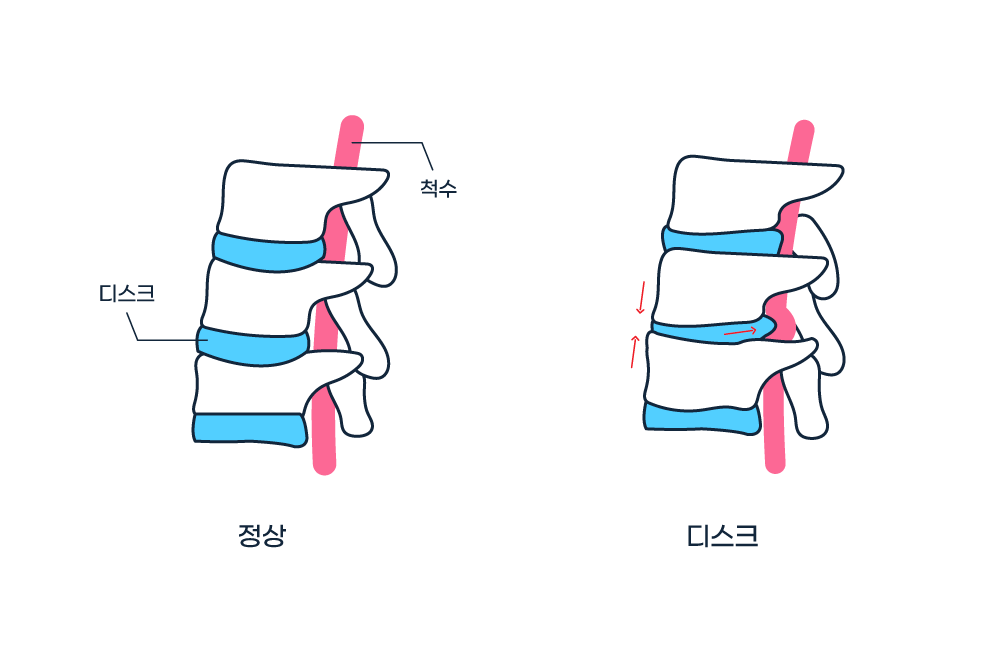

소위 디스크라고 잘 알려진 추간판탈출증은 척추뼈와 척추뼈 사이에 존재하는 추간판(디스크)이 어떤 원인에 의해 손상을 입으면서내부의 수핵이 밖으로 밀려 나와 주위 조직, 특히 척추신경을 압박하면서 통증 등의 증상을 유발하는 질환입니다.